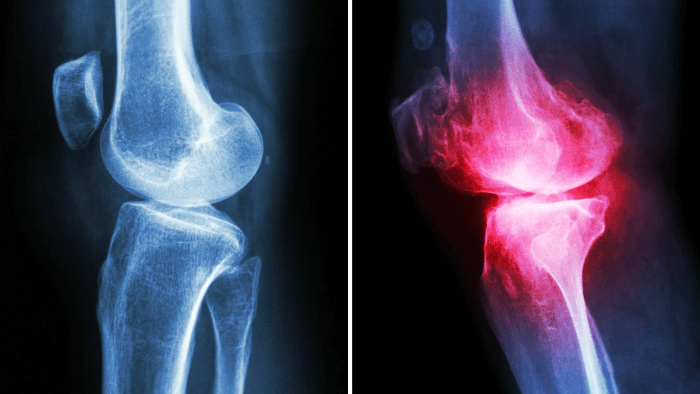

What is Arthritis?

x-ray of two hands with red spots over the joints indicating arthritis

At its core, arthritis is a term that simply means inflammation of the joints, but that definition doesn’t quite capture how complex or varied it really is. There are over 100 different types of arthritis, each with its own triggers, symptoms, and long-term consequences. (12) Some forms are purely mechanical, while others are driven by immune dysfunction. Some come on slowly and quietly over the years, and others seem to appear overnight. What they all have in common is this, they compromise your joints.

Here’s how arthritis shows up in most people (13, 14):

Recognizing Rheumatoid Arthritis

RA is notorious for being sneaky in its early stages. It might feel like a bad flu or vague joint pain at first. But it usually becomes more distinct over time.

Here’s what to watch for (42):

• Symmetrical joint pain: Unlike OA, RA typically affects joints on both sides of the body (e.g. both wrists or both knees).

• Morning stiffness lasting longer than 30–60 minutes

• Swollen, warm, and tender joints: especially in the fingers, wrists, elbows, and knees.

• Fatigue, low-grade fever, weight loss: systemic inflammation affects the whole body.

• Progressive joint deformities: like ulnar deviation in the hands or joint subluxations.

• Flare-ups and remissions: Symptoms can worsen suddenly and then calm down for a while.

RA can appear at any age, though it most commonly shows up between ages 30 and 60. (42) Women are affected about three times more often than men.